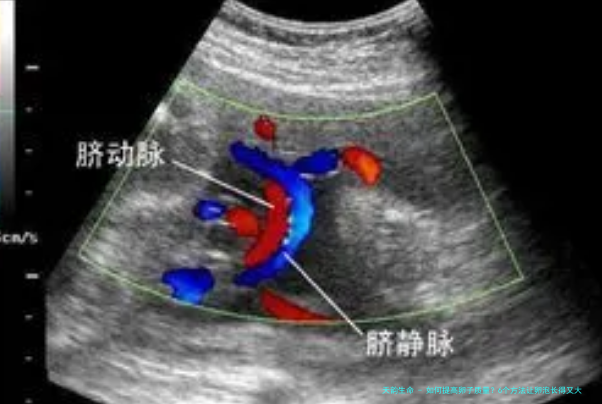

试管婴儿医生象征,在生活中我们可以用下面列举6个方法改善卵子质量,让卵泡长得又大又圆。